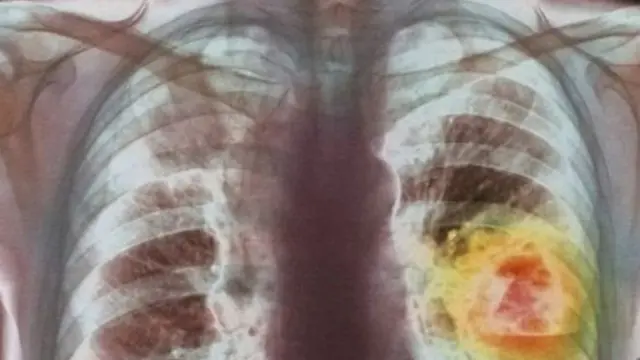

डॉक्टरांच्या मते फुफ्फुसाच्या कॅन्सरचे दोन प्रकार असतात. ते म्हणजे स्मॉल सेल कॅन्सर आणि नॉन स्मॉल सेल कॅन्सर.

स्मॉल सेल कॅन्सर झपाट्याने पसरतो. मात्र नॉन स्मॉल सेल कॅन्सर हा स्मॉल सेल कॅन्सरच्या तुलनेत कमी वेगाने पसरतो.